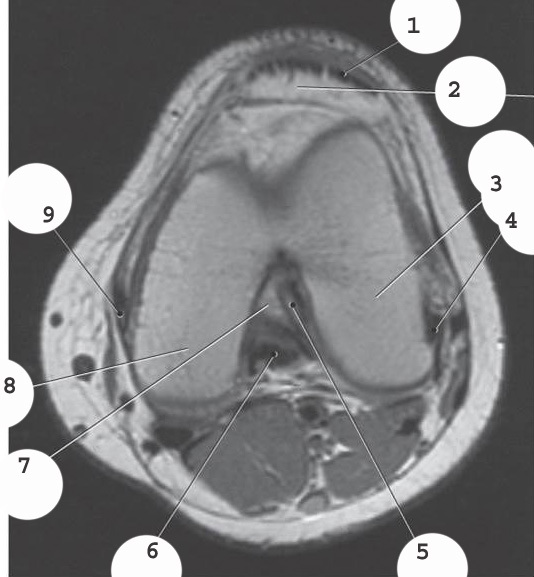

1

quadricep tendon

2

patella

3

lateral condyle

4

lateral colateral ligament

5

anterior cruciate ligament

ACL

6

posterior cruciate ligament

PCL

7

intercondylar fossa